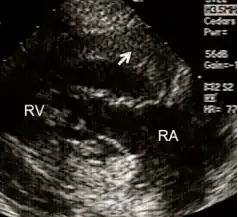

- RV inflow view showing marked right ventricular hypertrophy

Echocardiography can be used to directly visualise right ventricular wall thickness. The preferred technique is the trans-oesophageal approach giving a view of 4 chambers. The normal thickness of a right ventricular free wall ranges from 2-5 millimetres, with a value above 5 mm considered to be hypertrophic.[11]